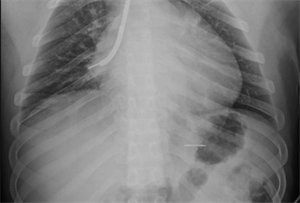

10月18日夜间急诊,来了一位14岁小患者,他在将手表零件放口中玩耍时,不慎吸入气管内。气管内异物是十分危急的,随时可能危及生命。小患者自觉胸闷不适,不时有咳嗽。急诊胸片和CT可以清晰地显示位于右中叶内侧段一长约2.3cm针形异物,两端较尖,急诊科医生程争启紧急联系呼吸与危重症医学科会诊,白克林主任考虑金属异物锐利可能损伤肺内血管造成大出血,准备急诊行内镜取异物。疼痛科、内镜室医务人员迅速反应,立即从家中赶往医院,争分夺秒做好各种术前准备工作。